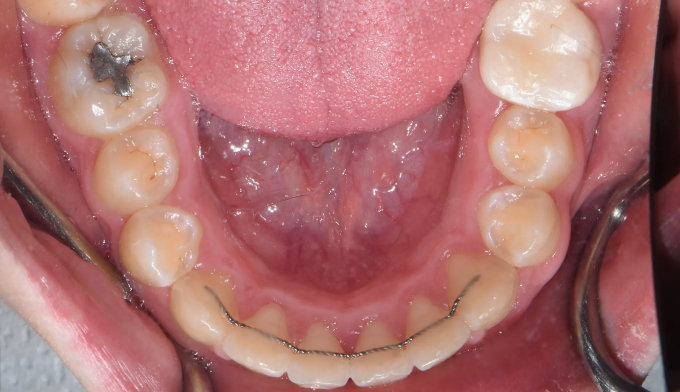

Before

앞니가 돌출되어있고, 특히 전반적으로 양치질이 부족하여 잇몸이 모두 부어있는 상태입니다.

치아들의 배열이 고르지 못한 상태에서는 양치질이 더욱 어려워지므로 구강위생상태에 더 신경을 써야 합니다.